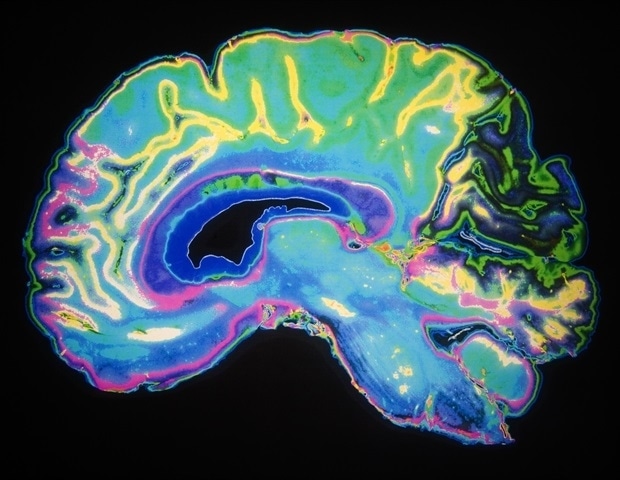

Χρησιμοποιώντας λογισμικό, οι επιστήμονες δημιούργησαν λεπτομερείς αναπαραστάσεις εγκεφάλων βασισμένες σε απεικονίσεις MRI από 21 ανθρώπινους ασθενείς. Ύστερα, σχεδίασαν ένα σετ ηλεκτροδίων προσαρμοσμένων στις συγκεκριμένες δομές των εγκεφάλων, πριν προβούν στην 3D εκτύπωση και των μοντέλων αυτών. Το αποτέλεσμα είναι βιοηλεκτρόδιοι που ταιριάζουν καλύτερα στον εγκέφαλο του ασθενούς σε σύγκριση με τις παραδοσιακές σχεδιάσεις.

Η επιφάνεια του ανθρώπινου εγκεφάλου, με τις χαρακτηριστικές πτυχές της, δημιουργείται μέσω μιας διαδικασίας που ονομάζεται γυρίφωση. Οι πτυχώσεις αυτές επιτρέπουν την ταχεία επικοινωνία των κυττάρων και διευκολύνουν την τοποθέτηση ενός σχετικά μεγάλου οργάνου εντός του κρανίου. Под τις προκαθορισμένες πτυχές, ωστόσο, η διάταξη των γυρικών και αυλών ποικίλλει σημαντικά από άτομο σε άτομο – μια διαφοροποίηση που, σύμφωνα με τον Dr. Tao Zhou, δεν λαμβάνεται υπόψη από τις παραδοσιακές λύσεις.